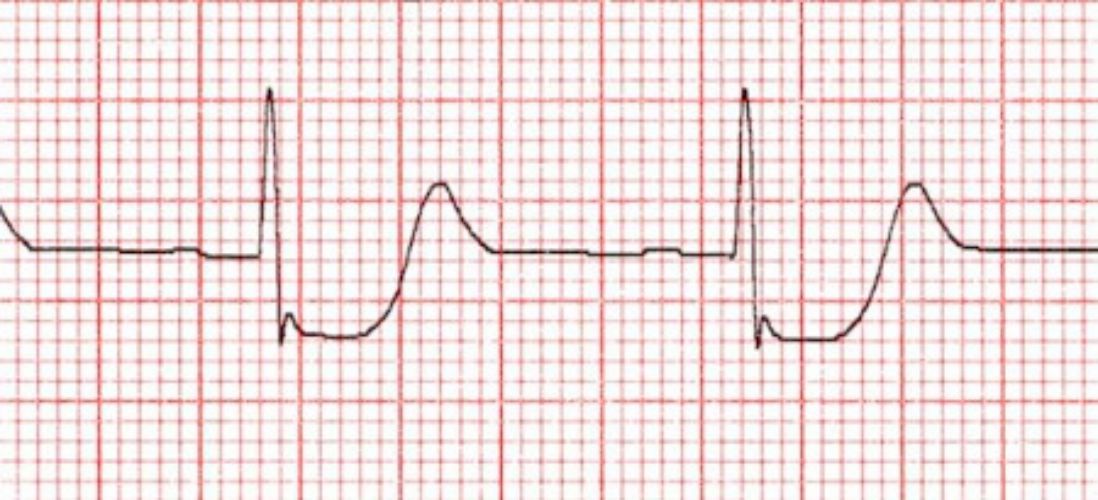

Appearance of leads V1-V2 suggestive of STEMI in Posterior MI. Notice how it appears as ST-depression on routine 12-lead EKG.

• New ST elevation at the J point in 2 contiguous leads > 1 mm (0.1 mV) in all leads except V2–V3

• New ST elevation V2–V3 of >= 2 mm in men younger than 40 years or >= 1.5 mm in women

• New, or presumed new, left bundle branch block

Posterior MI may be a STEMI, but appear as ST-depression on a routine 12-lead EKG. Confirm STEMI by obtaining a R-sided EKG.